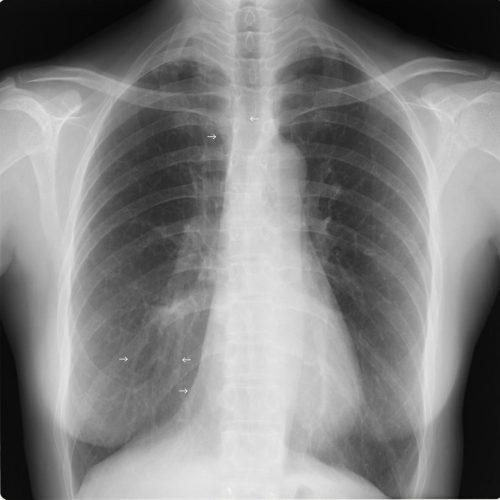

肺野の含気過多があり細気管支炎様のレントゲン像だが、同時に上縦隔右気管支上の部分が反対側の左と比べてやや白く透過性が悪くなっている。このような場合気管支S1もしくはS2の浸潤影初期のことがある。

5日後に確認したレントゲン像を下に提示する。